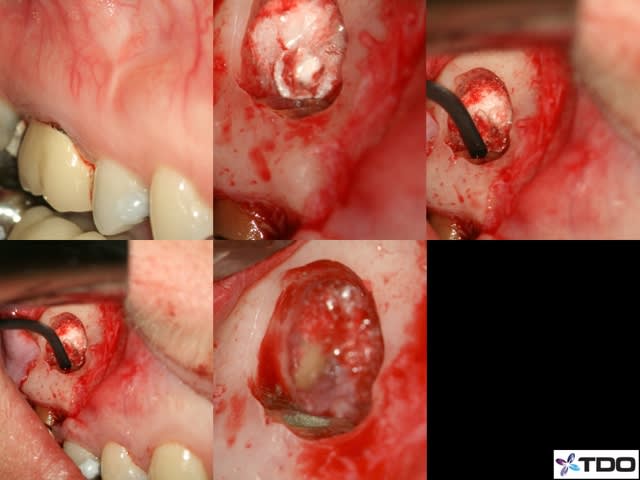

Pour la lésion endo paro sur la 46, j'aurai certainement extrait d'emblée.

Comme tu as fait un super boulot en endo, autant faire le max en paro maintenant. Il conviendrait de saquer la 48 mésioversée et lors de cette chir décoller un peu en antérieur, surfacer la racine distale et la zone inter radiculaire de la 46. Pas de matériau de comblement car il n'y a plus de paroi osseuse pour le soutenir.

Je reste tout de même pessimiste pour cette dent étant donné qu'il semble y avoir du tartre sur toute la hauteur de la racine distale. Quelle est la possibilité de réattache dans ce cas??? noah?

Je pense qu'il est bon de rappeler que tous nos actes endodontiques et parodontaux (pour ne citer qu'eux) sont basées sur des principes biologiques, qu'il est impossible de contourner.

La cicatrisation parodontale a largement été décrite et repose sur plusieurs impératifs cellulaires : présence de paroies osseuses, présence d'un ligt parodontal intact. Est ce des éléments présents dans le cas présenté .... non.

Tu peux toujours combler avec de la poudre de perlinpimpin, mais dépêches toi de faire une radio juste à la fin de ta chir, c'est le seul moment où tu auras le sentiment d'avoir régénéré de l'os !!

Il est tout aussi important de parler de pronostic que de parler de diagnostic. Et il y a des fois où l'extraction est la seule issue...